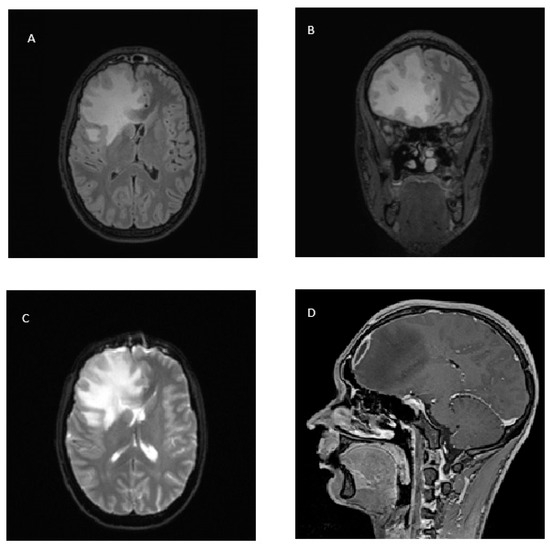

2. Case Report